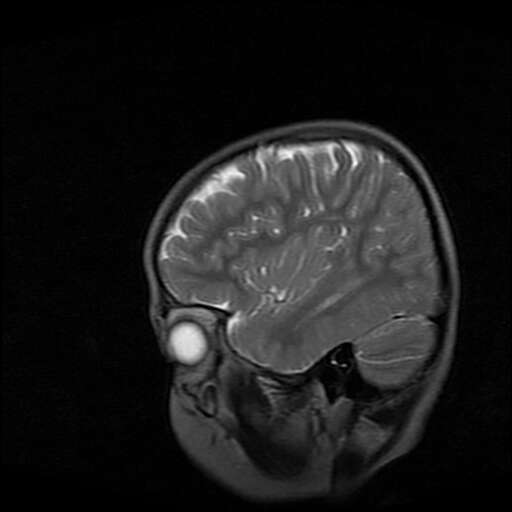

女,7岁,三岁才说话、走路。现智力尚可,走路不稳。临床怀疑大脑发育不全。

脑折质变薄,双侧侧脑室稍扩张,支持考虑脑折质发育不良

侧脑室周围白质软化症。

考虑胼胝体发育不全,髓鞘形成不良。

支持考虑胼胝体发育不全,髓鞘形成不良。

脑裂畸形伴灰质异位

侧脑室周围白质数量减少,侧脑室不对称性扩大,左侧侧脑室后角呈方形改变,脑沟加深,结合临床考虑脑室周围白质软化症(pvl)。期待结果!

只看出灰质异位

支持脑白质发育不良。